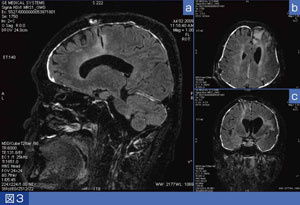

図3に、髄膜炎を疑われた頭部造影FLAIR-Cubeの画像を示す。Cubeは、IRパルスを付加することでFLAIRも撮像可能である。典型的な髄膜炎の所見ではないが、硬膜が造影されているのがわかる。約5分の撮像で、どの撮像断面にもリフォーマット可能である。従来は、FLAIRを2方向撮像するのに約6分かかっていたが、Cubeでは、ほぼ同一の撮像時間で得られる情報は飛躍的に増加する。このFLAIR-Cubeの画質はとても素晴らしく、今後、多発性硬化症(MS)などの変性疾患にも応用する予定である。

図3 髄膜炎疑い症例の頭部造影FLAIR-Cube画像 a:FLAIR-Cube矢状断元画像 b:FLAIR-Cube再構成横断像 c:FLAIR-Cube再構成冠状断像

a:FLAIR-Cube矢状断元画像

b:FLAIR-Cube再構成横断像

c:FLAIR-Cube再構成冠状断像